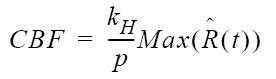

| CBF |  |  |

| table legend | p = density of brain tissue R(t) = Residue function kH = correction factor | |

Relative Blood Flow

Relative Corrected Blood Flow (rCBF) quantifies the volume of arterial blood delivered to a given mass of tissue per unit time, thus representing instantaneous capillary flow in tissue.